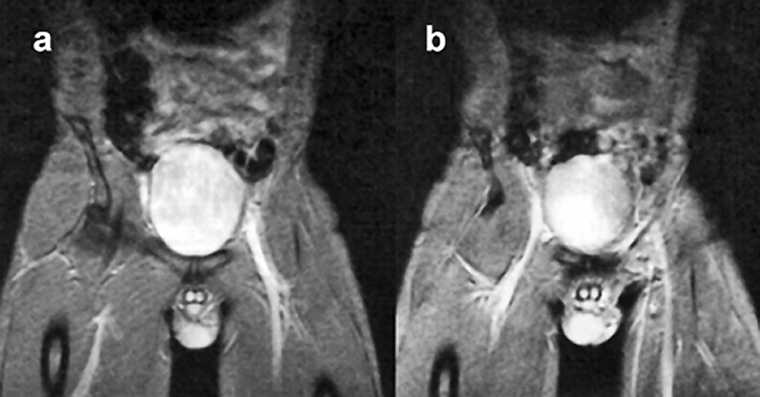

Figure 14-09 shows an example of high-signal blood in an examination of the pelvis. This behavior has been exploited for cardiac studies (Figure 14-10) and is fun­da­­men­tal to magnetic resonance angiography.

Figura 14-09:

In gradient-echo images, flowing blood appears bright. Note: These images are plain GRE ima­ges; they are not (yet) MR angiograms. Parameters: B₀ = 0.5 T; TR = 400 ms, TE = 28 ms, FA = 20°.